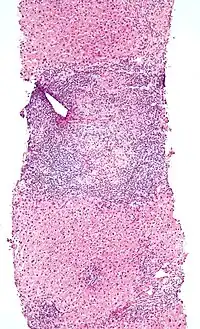

| Micrograph of PBC showing bile duct inflammation and injury, H&E stain | |

On microscopic examination of liver biopsy specimens, PBC is characterized by chronic, nonsuppurative inflammation, which surrounds and destroys interlobular and septal bile ducts. These histopathologic findings in primary biliary cholangitis include:[31]

- Inflammation of the bile ducts, characterized by intraepithelial lymphocytes

- Periductal epithelioid granulomas.

- Proliferation of bile ductules

- Fibrosis (scarring)